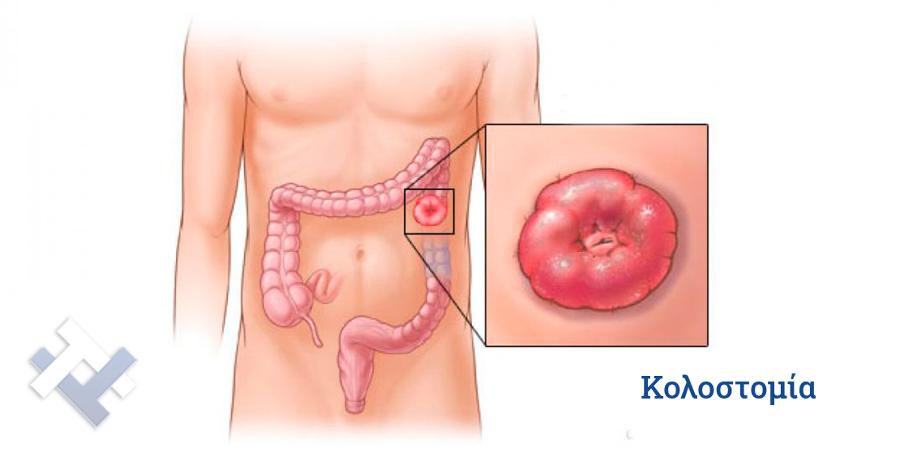

- Κολοστομίες

- Κολοστομίες

Ο Γενικός Χειρουργός Λιάγκος Γεώργιος MD PhD εκτελεί τις επεμβάσεις Λαπαροσκοπικά, Ενδοσκοπικά, Ανοιχτά Ελάχιστα Επεμβατικά και με Laser. Η θεραπεία εξατομικεύεται σε κάθε ασθενή ανάλογα με τις ανάγκες του. Αναλαμβάνει περιπτώσεις όπως κήλες και κοιλιοκήλες (αντιμετώπιση βουβωνοκήλης, αντιμετώπιση ομφαλοκήλης, θεραπεία επιγαστρικής κήλης, κήλη των αθλητών (Σύνδρομο κοιλιακών προσαγωγών), αντιμετώπιση μετεγχειρητικής κήλης, θεραπεία Μηροκήλης), πέτρες στη χοληδόχο κύστη, λαπαροσκοπική χολοκυστεκτομή, αντιμετώπιση Κύστη Κόκκυγος με λέιζερ (laser), παθήσεις πρωκτού, χειρουργική laser σύγχρονων κυκλικών ινών (αιμορροΐδες αντιμετώπιση, θεραπεία αιμορροϊδων με laser (LHP), αφαίρεση αιμορροΐδων με υπερήχους (HALL-RAR), χωρίς Χειρουργείο με ελαστικούς δακτυλίους (Τεχνική BARON-RBL), θεραπεία ραγάδας πρωκτού (Ραγάδα δακτυλίου), θεραπεία περιεδρικού συριγγίου, θεραπεία περιεδρικού αποστήματος, κονδυλώματα πρωκτού Θεραπεία, δερματικό ράκος (Skin tag) εκτομή, αντιμετώπιση Kνησμού, καρκίνος πρωκτού θεραπεία), παθήσεις Δέρματος, χειρουργική με laser CO2, αφαίρεση μορφωμάτων δέρματος - βιοψίες, αφαίρεση ελιάς (Σπίλου), σμηγματογόνος κύστης θεραπεία, αφαίρεση λιπώματος, είσφρυση όνυχος χειρουργείο, καρκίνος δέρματος θεραπεία, οξεία σκωληκοειδίτιδα, παθήσεις Λεπτού και Παχέος Εντέρου, ειλεός λεπτού εντέρου, εκκολπωμάτωση (Εκκολπωματίτιδα) σιγμοειδούς, καρκίνος παχέος εντέου, κολοστομίες, port χημειοθεραπείας κ.α.

Ο Γενικός Χειρουργός Λιάγκος Γεώργιος MD PhD εκτελεί τις επεμβάσεις Λαπαροσκοπικά, Ενδοσκοπικά, Ανοιχτά Ελάχιστα Επεμβατικά και με Laser. Η θεραπεία εξατομικεύεται σε κάθε ασθενή ανάλογα με τις ανάγκες του. Αναλαμβάνει περιπτώσεις όπως κήλες και κοιλιοκήλες (αντιμετώπιση βουβωνοκήλης, αντιμετώπιση ομφαλοκήλης, θεραπεία επιγαστρικής κήλης, κήλη των αθλητών (Σύνδρομο κοιλιακών προσαγωγών), αντιμετώπιση μετεγχειρητικής κήλης, θεραπεία Μηροκήλης), πέτρες στη χοληδόχο κύστη, λαπαροσκοπική χολοκυστεκτομή, αντιμετώπιση Κύστη Κόκκυγος με λέιζερ (laser), παθήσεις πρωκτού, χειρουργική laser σύγχρονων κυκλικών ινών (αιμορροΐδες αντιμετώπιση, θεραπεία αιμορροϊδων με laser (LHP), αφαίρεση αιμορροΐδων με υπερήχους (HALL-RAR), χωρίς Χειρουργείο με ελαστικούς δακτυλίους (Τεχνική BARON-RBL), θεραπεία ραγάδας πρωκτού (Ραγάδα δακτυλίου), θεραπεία περιεδρικού συριγγίου, θεραπεία περιεδρικού αποστήματος, κονδυλώματα πρωκτού Θεραπεία, δερματικό ράκος (Skin tag) εκτομή, αντιμετώπιση Kνησμού, καρκίνος πρωκτού θεραπεία), παθήσεις Δέρματος, χειρουργική με laser CO2, αφαίρεση μορφωμάτων δέρματος - βιοψίες, αφαίρεση ελιάς (Σπίλου), σμηγματογόνος κύστης θεραπεία, αφαίρεση λιπώματος, είσφρυση όνυχος χειρουργείο, καρκίνος δέρματος θεραπεία, οξεία σκωληκοειδίτιδα, παθήσεις Λεπτού και Παχέος Εντέρου, ειλεός λεπτού εντέρου, εκκολπωμάτωση (Εκκολπωματίτιδα) σιγμοειδούς, καρκίνος παχέος εντέου, κολοστομίες, port χημειοθεραπείας κ.α.